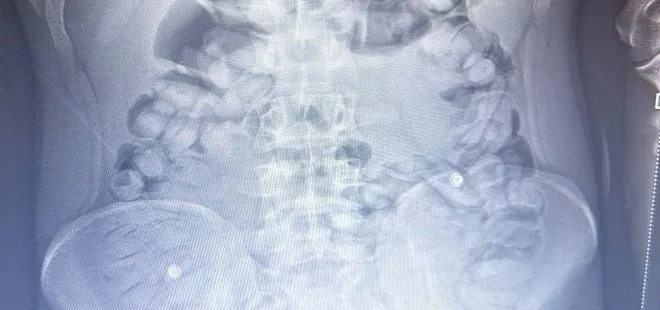

"Uyuşturucu madde ticareti ve sevkiyatına yönelik yapılan çalışmalar neticesinde 13.11.2023 tarihinde tespit edilen yolcu otobüsünde durumunlarından şüphelenilenerek uyuşturucu madde yutmuş olabileceği değerlendirilen ve İlimiz Şehir Hastanesinde iç beden muayenesi yaptırılan S.A. (2006 doğumlu) isimli şahıstan toplam 1 kilo 134 gram Afyon Sakızı maddesi ele geçirilmiş, konuyla ilgili adli mercilere sevk edilen şahıs tutuklanarak cezaevine teslim edilmiştir.